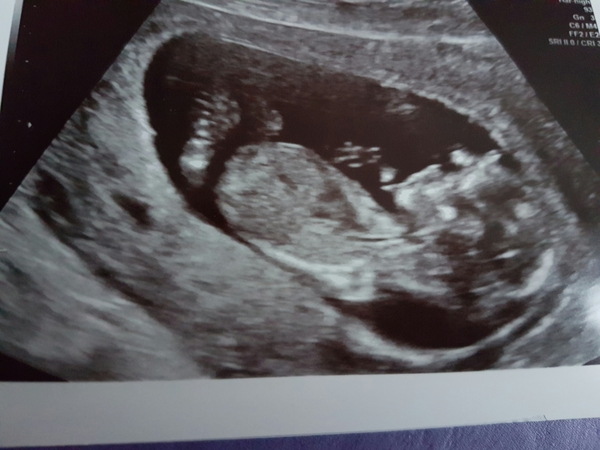

MundayCakes85 · 24/11/2016 10:53

Baby snoozing the whole time, everything where it should be! EDD moved forward to 2nd June so 12.6 by their calculations! Now trying to explain to DD where the baby is- she wants to get a torch to look in my belly button 😂😂

munday great pic. Your dd is so sweet! Bless her!

Munday that is so cute of your DD! How old is she?

Munday lovely scan pic! If I ask DS where my baby is he rubs my tummy, but yesterday he then rubbed his own and nodded when I asked if there was a baby in his tummy Grin

Congratulations Munday! It's such a relief isn't it!

All well here, hyperactive single bean who didn't stay still at all! Obviously beautiful, looks a little like an alien with brain matter, a heart, a spine and a little bum. I'll post scan pic if I can work out how to attach.

No idea if the nub is visible, I don't mind people guessing the sex!